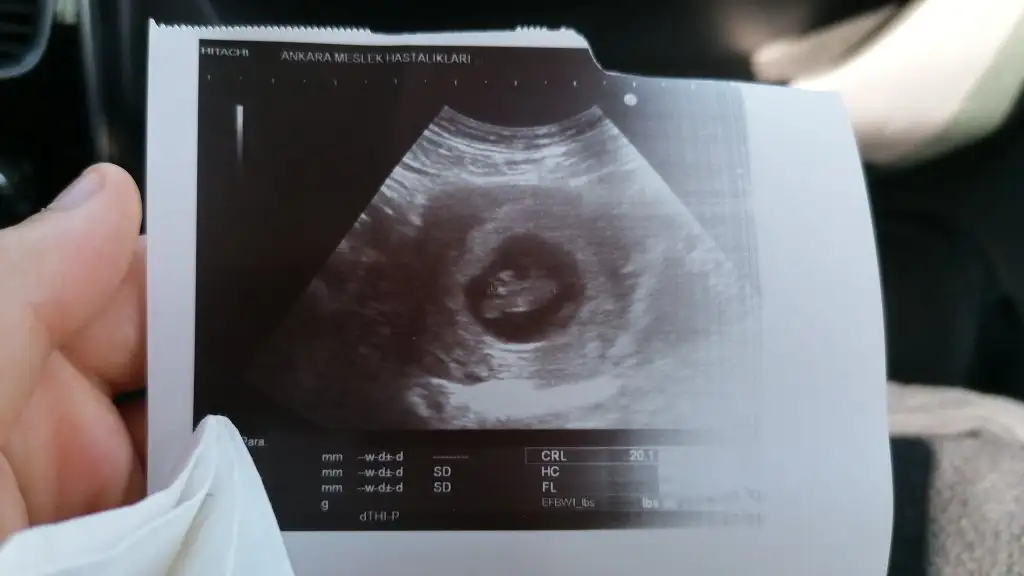

Buda ilk az once gonderdigim bugunkiydi 12 haftalik. Simdi attigim 7 haftalikValla hicbisey gormuyorum kese nerde gııı

Buda ilk az once gonderdigim bugunkiydi 12 haftalik. Simdi attigim 7 haftalik

Canim valla plesantan net degilEki Görüntüle 3073453

Teşekkür ederim yine deCanim valla plesantan net degil